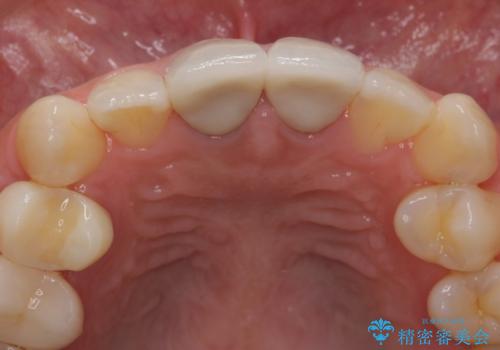

神経の方は問題なさそうだったため、患者様の希望でやりなおさず、土台とセラミック治療を行いました。

- 32万円(税別) 上顎両側1 ファイバーコア、仮歯、ジルコニアクラウン(スペシャル)費用は治療当時の料金となります

歯茎の黒ずみに関しては、中の歯の根が変色して透けている状態のため、変えることは難しいです。

笑っても歯肉が見えにくい方でしたので、問題ありませんでした。